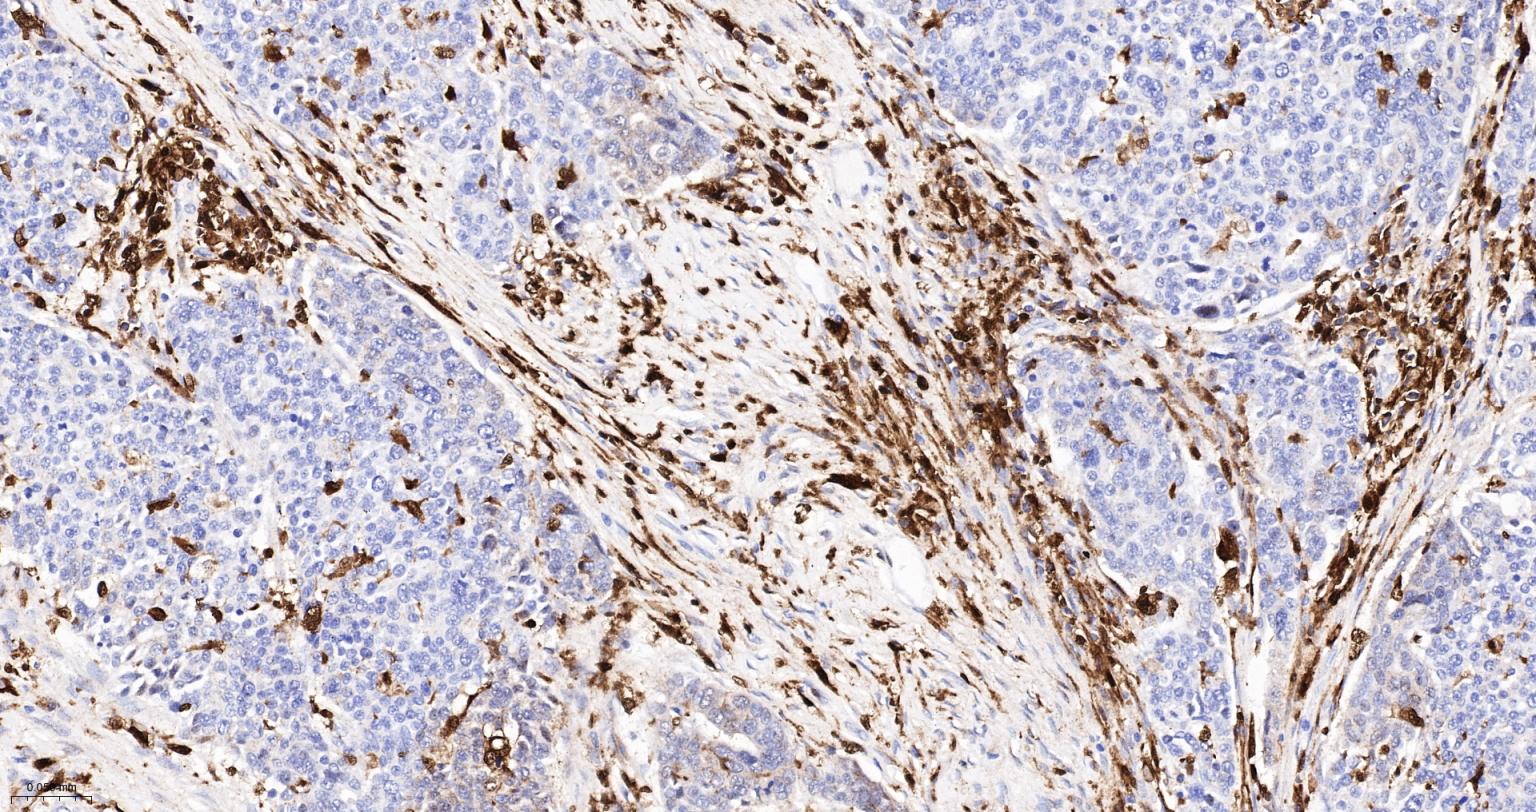

Paraformaldehyde-fixed, paraffin embedded Human Liver; Antigen retrieval by boiling in sodium citrate buffer (pH6.0) for 15 min; The section was incubated with CD16 Monoclonal Antibody, Unconjugated (bsm-54679R) at 1:500 overnight at 4°C, followed by conjugation to the bs-0295G-HRP and DAB (C-0010) staining.